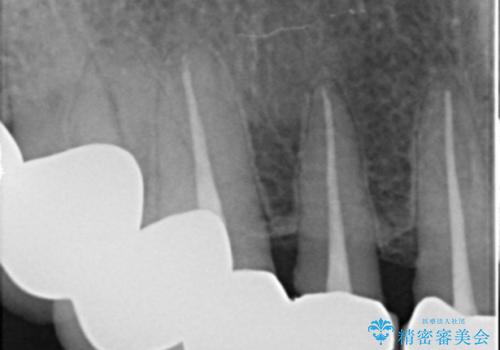

上の前歯6本はメタルボンドクラウン(内側が金属の被せ物)で補綴されており、顕著な歯肉退縮を認めました。

被せ物を除去したところ根管治療後の処置が不十分であったため、ファイバーコア(金属を用いない強くてしなやか材質の土台)を植立したのち、ジルコニアセラミッククラウンによる治療を行いました。